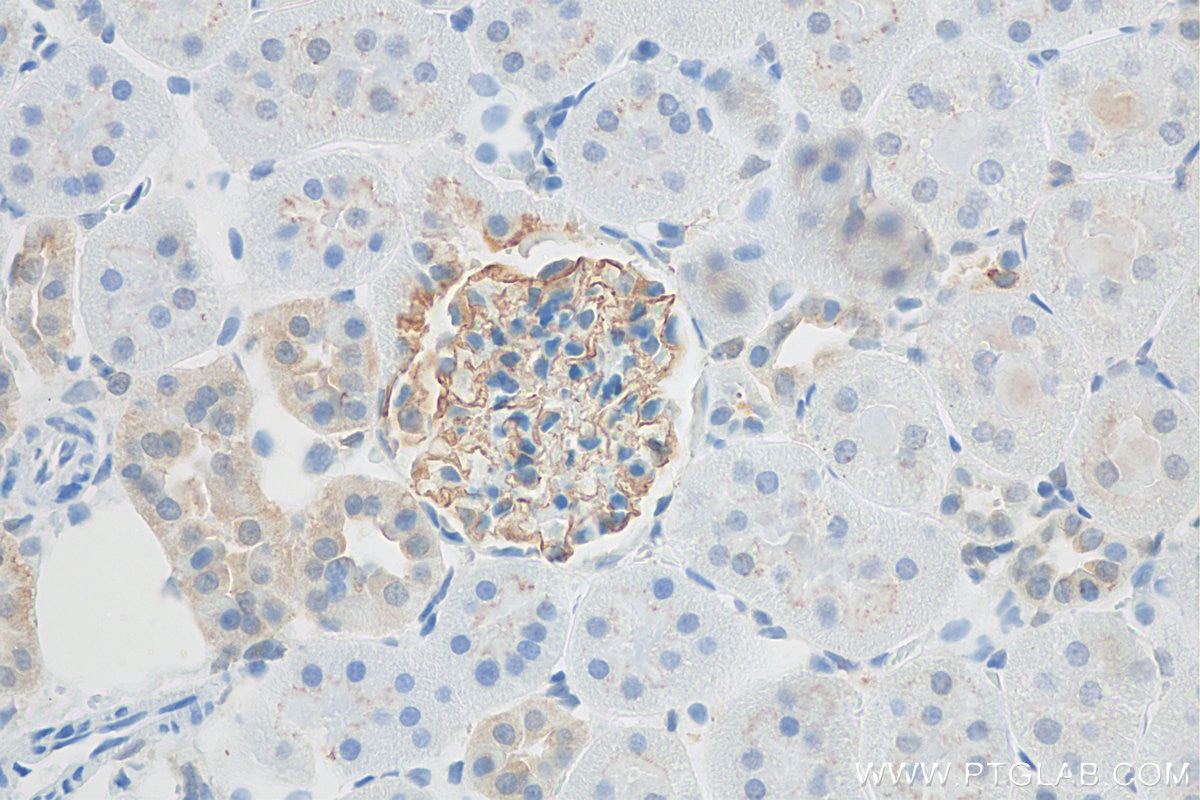

| Positive IHC detected in | rat kidney tissue Note: suggested antigen retrieval with TE buffer pH 9.0; (*) Alternatively, antigen retrieval may be performed with citrate buffer pH 6.0 |

| Immunohistochemistry (IHC) | IHC : 1:200-1:800 |

NPHS2 (also known as Podocin) is a membrane protein located on the podocyte foot process and is the critical component of the glomerular filtration barrier. Mutations of NPHS2 cause recessive steroidresistant nephrotic syndrome. Two isoforms of NPHS2 exist with molecular weights of 42 kDa and 35 kDa, respectively. (PMID: 21499232)